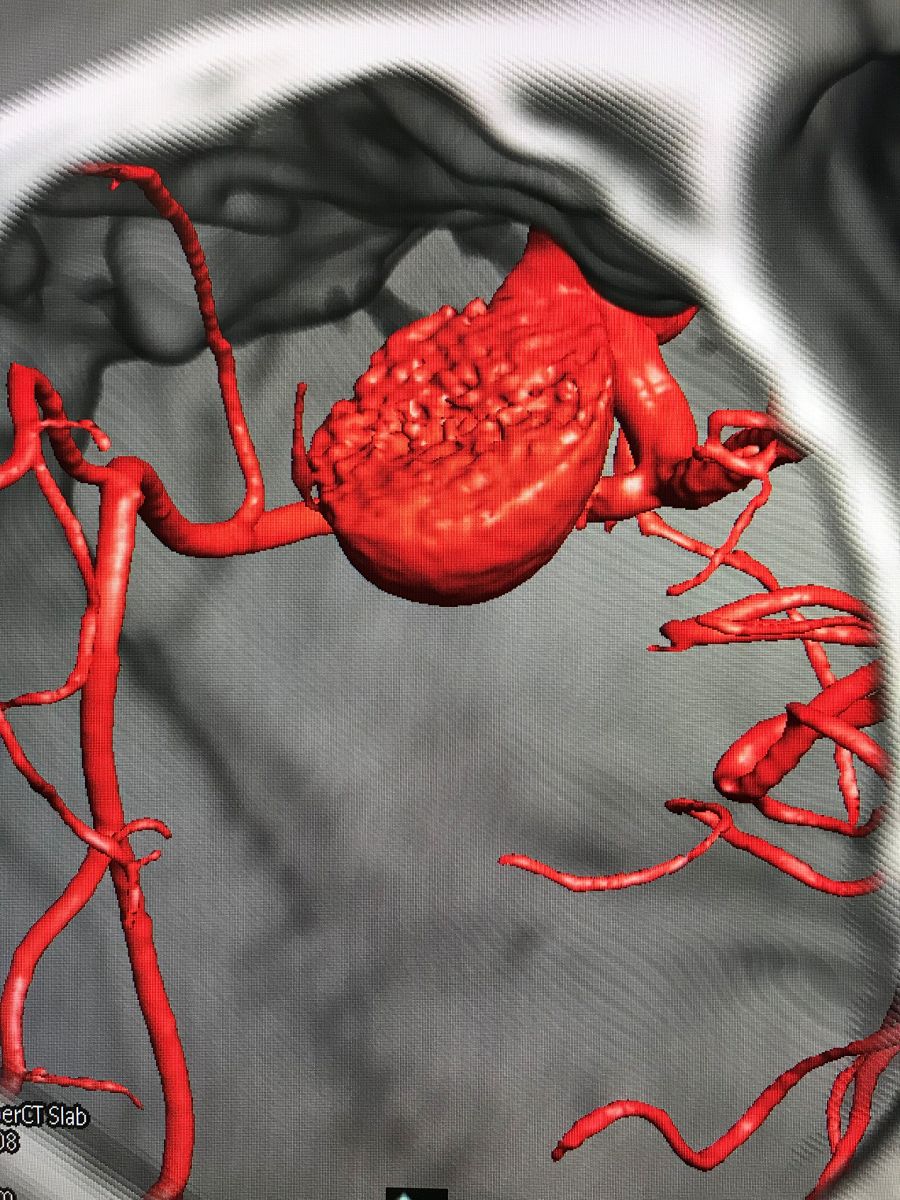

2018.5.8患者全麻下行临时球囊阻断下右侧眼动脉大动脉瘤夹闭术。术中取右侧额外侧入路,形成骨瓣约4*4cm大小,牵开额底,切开蛛网膜释放脑脊液后即见动脉瘤。术中所见瘤体与周边结构解剖关系和术前融合图像完全一致。瘤体表面张力较高,牵开瘤体困难,无法暴露瘤颈和近心端动脉。

术中动脉瘤所见

术前虚拟瘤体大小

再次探查动脉瘤发现瘤体表面张力明显下降,探针分离瘤颈,以2枚直动脉瘤夹792+760夹闭瘤颈。解除球囊阻断后,动脉瘤表面张力无回升,穿刺瘤体无活动性出血。荧光造影提示瘤体无显影,载瘤动脉血流通畅,无明显狭窄,各分支保留完好。切除部分瘤体,视神经减压。DSA复查提示动脉瘤夹闭满意,全脑血管通畅后关颅。(球囊阻断时间约10分钟)

结合本病例,我们术前利用复合手术室飞利浦DSA血管机,造影后即刻行CT扫描。由于是在同一机器环境下完成的两种模态扫描,减少了伪影干扰,解剖结构电脑自动吻合,故影像融合精度极高。并且因为是双模态融合,可以用不同颜色标记血管和骨窗,增加了对比度,提高了分辨率,较CTA有明显优势。利用术前融合模拟手术入路,放大后观察发现动脉瘤体巨大,紧贴颅底和床突,缺乏至少2mm的近端阻断空间,术中需要磨除前床突。但术中发现动脉瘤表面张力极高,紧贴床突硬脑膜,高速磨钻操作存在巨大风险。而术中球囊阻断颈内动脉后,动脉瘤张力明显下降,依靠吸引器轻轻牵拉即可暴露出瘤颈,不必要磨除床突,降低了手术复杂度。